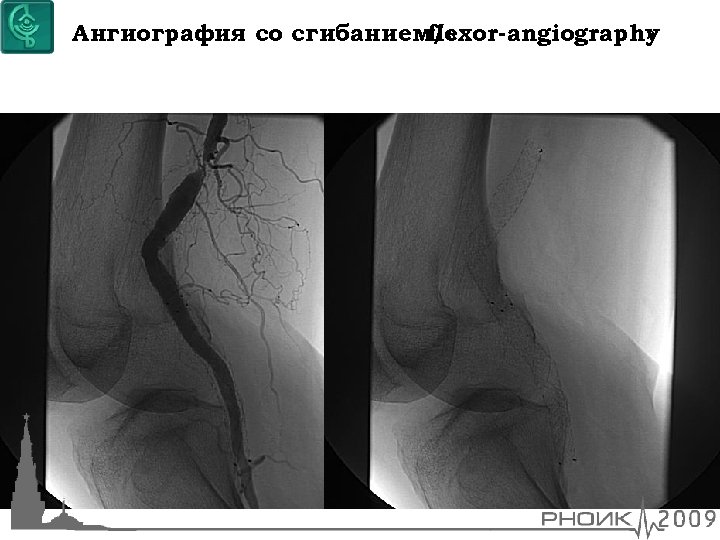

Ангиография со сгибанием/ « flexor-angiography »

Уникальность артерии Небольшой диаметр Часто встречаются окклюзии Длинный сегмент поражения Часто кальциноз стенок Частое поражение артерий притока и оттока • 4 силы действуют на артерию • • •

Геометрия артерии Силы, воздействующие на ПБА, разнообразны Растяжение/сокращение Сгибание Скручивание Сжатие